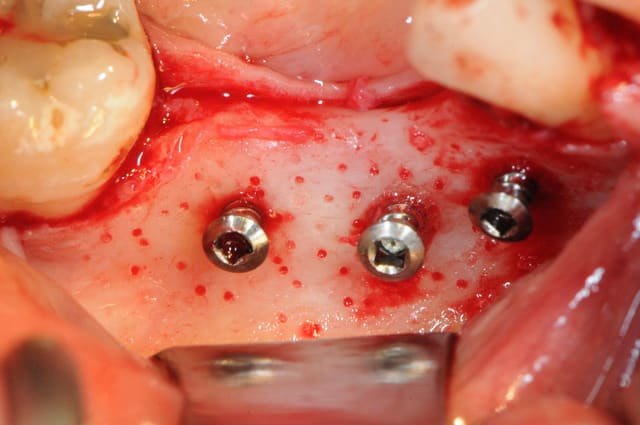

en faisant une carotte osseuse aujourd'hui sur une crête mandibulaire, j'ai bien cru que j'avais coupé le nerf alvéolaire inférieur.

je devais mettre un implant de 6mm là où il n'y avait que 3.5 à4mm d'os. le reste des spires devaient être laissées en supra crestal et une ROG verticale devait être réalisée avec des vis Fast et une mesh titane + recouvrement par une membrane de péricarde.

seulement aujourd'hui, la tréphine apès avoir traversé la corticale est rentrée comme dans du beurre. j'ai été surpris car je faisait très attention. la patiente n'a absolument pas bronché d'un cil. quand j'ai retiré la carotte il y avait un truc mou accroché dessous; le V3 !

on voit même sur la carotte la trace du nerf (photo)

au final j'ai replacé ma carotte et effectué ma ROG mais sans mettre mon implant.

en plus c'était la loose complète, j'ai du retirer mes mesh titanes car le lambeau s'est déchiré juste en face de la vis qui les maintenait.

j'ai revu la patiente en fin de soiré et finalement elle n'a pas de perte de sensibilité. attendons encore 72 heures pour être sure qu'il n'y ait pas de compression due à l'hématome.

si c'est le cas ce sera corticothérapie retard à haute dose!

non, la carotte c'était pour ne pas utiliser les forets ce qui me permet de diminuer le nombre de forage et de diminuer ainsi le risque de fraiser le nerf. autrement dit je fore directement au diamètre de l'implant et de l'enfoui que sur 3mm à peine.

je vous le confirme bien, le truc mou au fond du trou c'était bien le V3 et non une branche collatérale.

ensuite la carotte devait être broyée et utilisé avec du maxgraft ou biobank en recouvrement des spires de l'implant. le tout devant être recouvert avec le mesh titane et des vis pour faire piquet de tente.

le problème, c'est qu'une partie de la gencive s'est déchirée et que par conséquent, je ne pouvait pas avoir l'assurance de refermer hermétiquement le site d'intervention. j'ai préféré replacer la carotte (en travers) pour gagner 1mm en hauteur et recouvrir avec un peu d'os et une membrane.